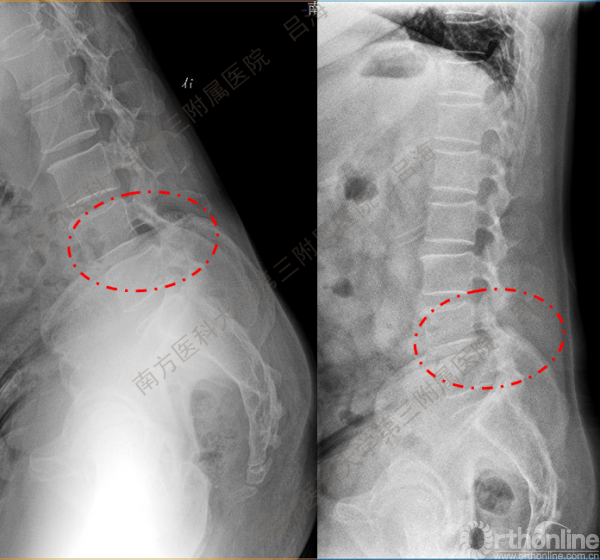

随着社会老龄化进程加快,胸腰椎退行性病变的治疗已经成为脊柱学术界的一个热点话题。MIS-TLIF手术可以治疗多种不同的胸腰椎退行性疾病,南方医科大学第三附属医院吕海教授结合病例为我们一一展示了该术式在治疗不同胸腰椎疾病时的具体手术过程。